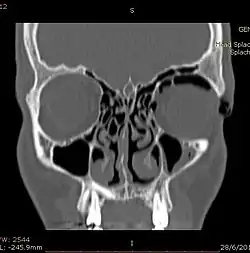

CT scan taken from the coronal plane demonstrating orbital emphysema.[39]